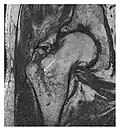

Proximal femoral fractures usually occur in osteoporotic patients, and their signs include subtle neck angulation, trabecular angulation, and subcapital impaction line. A frog-leg lateral view may be helpful if the greater trochanter is short enough. However, positioning can be difficult because of hip pain. In patients with strong suspicion of proximal femoral fracture and negative radiographs, MRI limited to coronal T1 W images and scintigraphy can be highly valuable (Figures 13 and 14). Such an option, with limited examination time, is cost-effective and allows reliable exclusion or confirmation of the diagnosis, preventing an unnecessary stay at the hospital or delayed treatment. Moreover, MRI helps to detect soft tissue abnormalities which are more frequently seen in femoral, acetabular, and pubic injuries than sacral lesions. Concomitant fractures are also frequently seen in typical pelvic sites.[1]

-

a -

b

Figure 14: Subcapital insufficiency fracture in a 55-year-old man with a left hip pain without a history of trauma. Anteroposterior and Lauenstein view radiographs centered on the left hip do not show an obvious fracture line, but mild acetabular osteophytosis was noted consistent with hip osteoarthritis (not shown). (a) Coronal T1-weighted MRI shows a linear low-signal band through the femoral neck corresponding to a fracture line (arrowheads). (b) Bone scintigraphy shows focal uptake (arrow) corresponding to the fracture.[1]